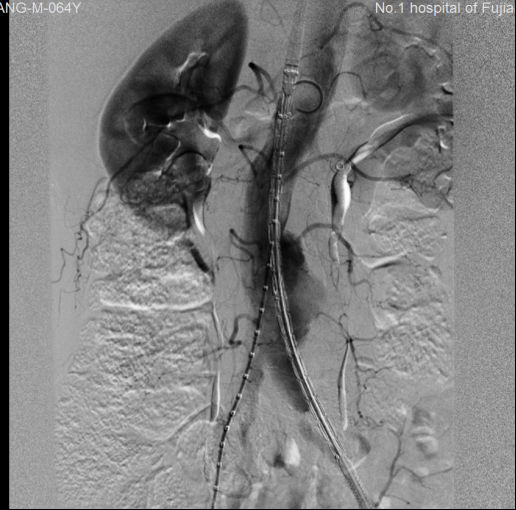

術(shù)前 術(shù)后

近期搶救的一例破裂腹主動(dòng)脈瘤就是一位臺(tái)灣退伍老兵,春節(jié)回長(zhǎng)樂探親前,在臺(tái)灣就已查出有腹主動(dòng)脈瘤,但沒有重視此事,可能因心情激動(dòng),突發(fā)腹痛,腹主動(dòng)脈瘤破裂送到我院救治,好在搶救及時(shí),現(xiàn)已安返臺(tái)灣。